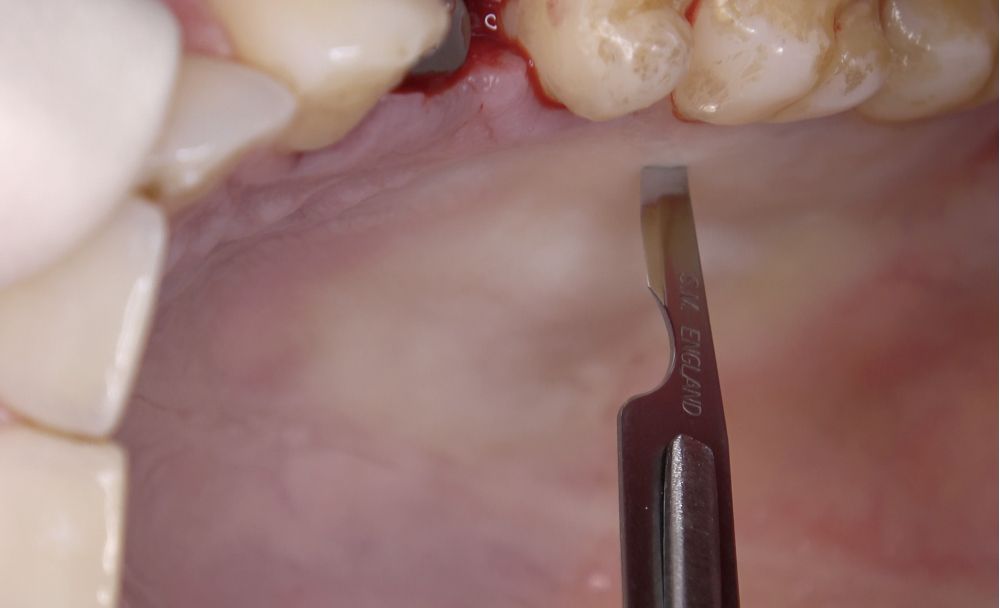

La cirugía plástica periodontal es el tratamiento de elección en casos de recesiones gingivales y defectos mucogingivales1,2. Actualmente, los injertos de tejido conectivo (ITC) son considerados el gold standard para la reconstrucción del tejido blando, debido a la estabilidad y biocompatibilidad que ofrecen a largo plazo2. Para la obtención del ITC, la técnica más común es la descrita por Zucchelli y cols.3, consistente en recolectar un injerto gingival libre que luego será desepitelizado extraoralmente. Existen otras alternativas en la obtención de este tipo de injertos, como la técnica en única incisión4, destinadas a minimizar la morbilidad en la zona donante. Sin embargo, el uso de ITC siempre implicará un área donante, generalmente palatina, aumentando la complejidad del procedimiento y las molestias del paciente durante el postoperatorio que, durante el proceso de cicatrización, podrían acarrear complicaciones como sangrado, dolor, infección o necrosis, mayormente relacionadas con la incapacidad de formar un coágulo sanguíneo estable5-8. Además de la sutura, se han empleado diversos agentes hemostáticos y cicatrizantes para lograr esta estabilización, como los adhesivos a base de cianoacrilato8. Entre las propiedades de estos adhesivos tisulares destacan su excelente capacidad hemostática, rápida adhesión a los tejidos y posibles cualidades bacteriostáticas8. Estudios previos indican que el uso de estos agentes en la cicatrización de la zona donante palatina tras la obtención de ITC con diferentes técnicas es prometedora9,10; sin embargo, la literatura sobre la cicatrización y respuesta del tejido en la zona donante palatina tras la obtención de injertos de tejido conectivo en incisión única aún es escasa. Por lo tanto, el objetivo del presente estudio fue evaluar y comparar el uso de sutura y cianoacrilato en la zona donante palatina tras la obtención de ITC.